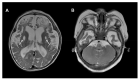

Coenzyme Q10 (CoQ10) is an endogenously synthesized lipid molecule. It is best known for its role as a cofactor within the mitochondrial respiratory chain where it functions in electron transfer and ATP synthesis. However, there are many other cellular pathways that also depend on the CoQ10 supply (redox homeostasis, ferroptosis and sulfide oxidation). The CoQ10 biosynthesis pathway consists of several enzymes, which are encoded by the nuclear DNA. The majority of these enzymes are responsible for modifications of the CoQ-head group (benzoquinone ring). Only three enzymes (PDSS1, PDSS2 and COQ2) are required for assembly and attachment of the polyisoprenoid side chain. The head-modifying enzymes may assemble into resolvable domains, representing COQ complexes. During the last two decades, numerous inborn errors in CoQ10 biosynthesis enzymes have been identified. Thus far, 11 disease genes are known (PDSS1, PDSS2, COQ2, COQ4, COQ5, COQ6, COQ7, COQ8A, COQ8B, COQ9 and HPDL). Disease onset is highly variable and ranges from the neonatal period to late adulthood. CoQ10 deficiency exerts detrimental effects on the nervous system. Potential consequences are neuronal death, neuroinflammation and cerebral gliosis. Clinical features include encephalopathy, regression, movement disorders, epilepsy and intellectual disability. Brain magnetic resonance imaging (MRI) is the most important tool for diagnostic evaluation of neurological damage in individuals with CoQ10 deficiency. However, due to the rarity of the different gene defects, information on disease manifestations within the central nervous system is scarce. This review aims to provide an overview of brain MRI patterns observed in primary CoQ10 biosynthesis disorders and to highlight disease-specific findings.